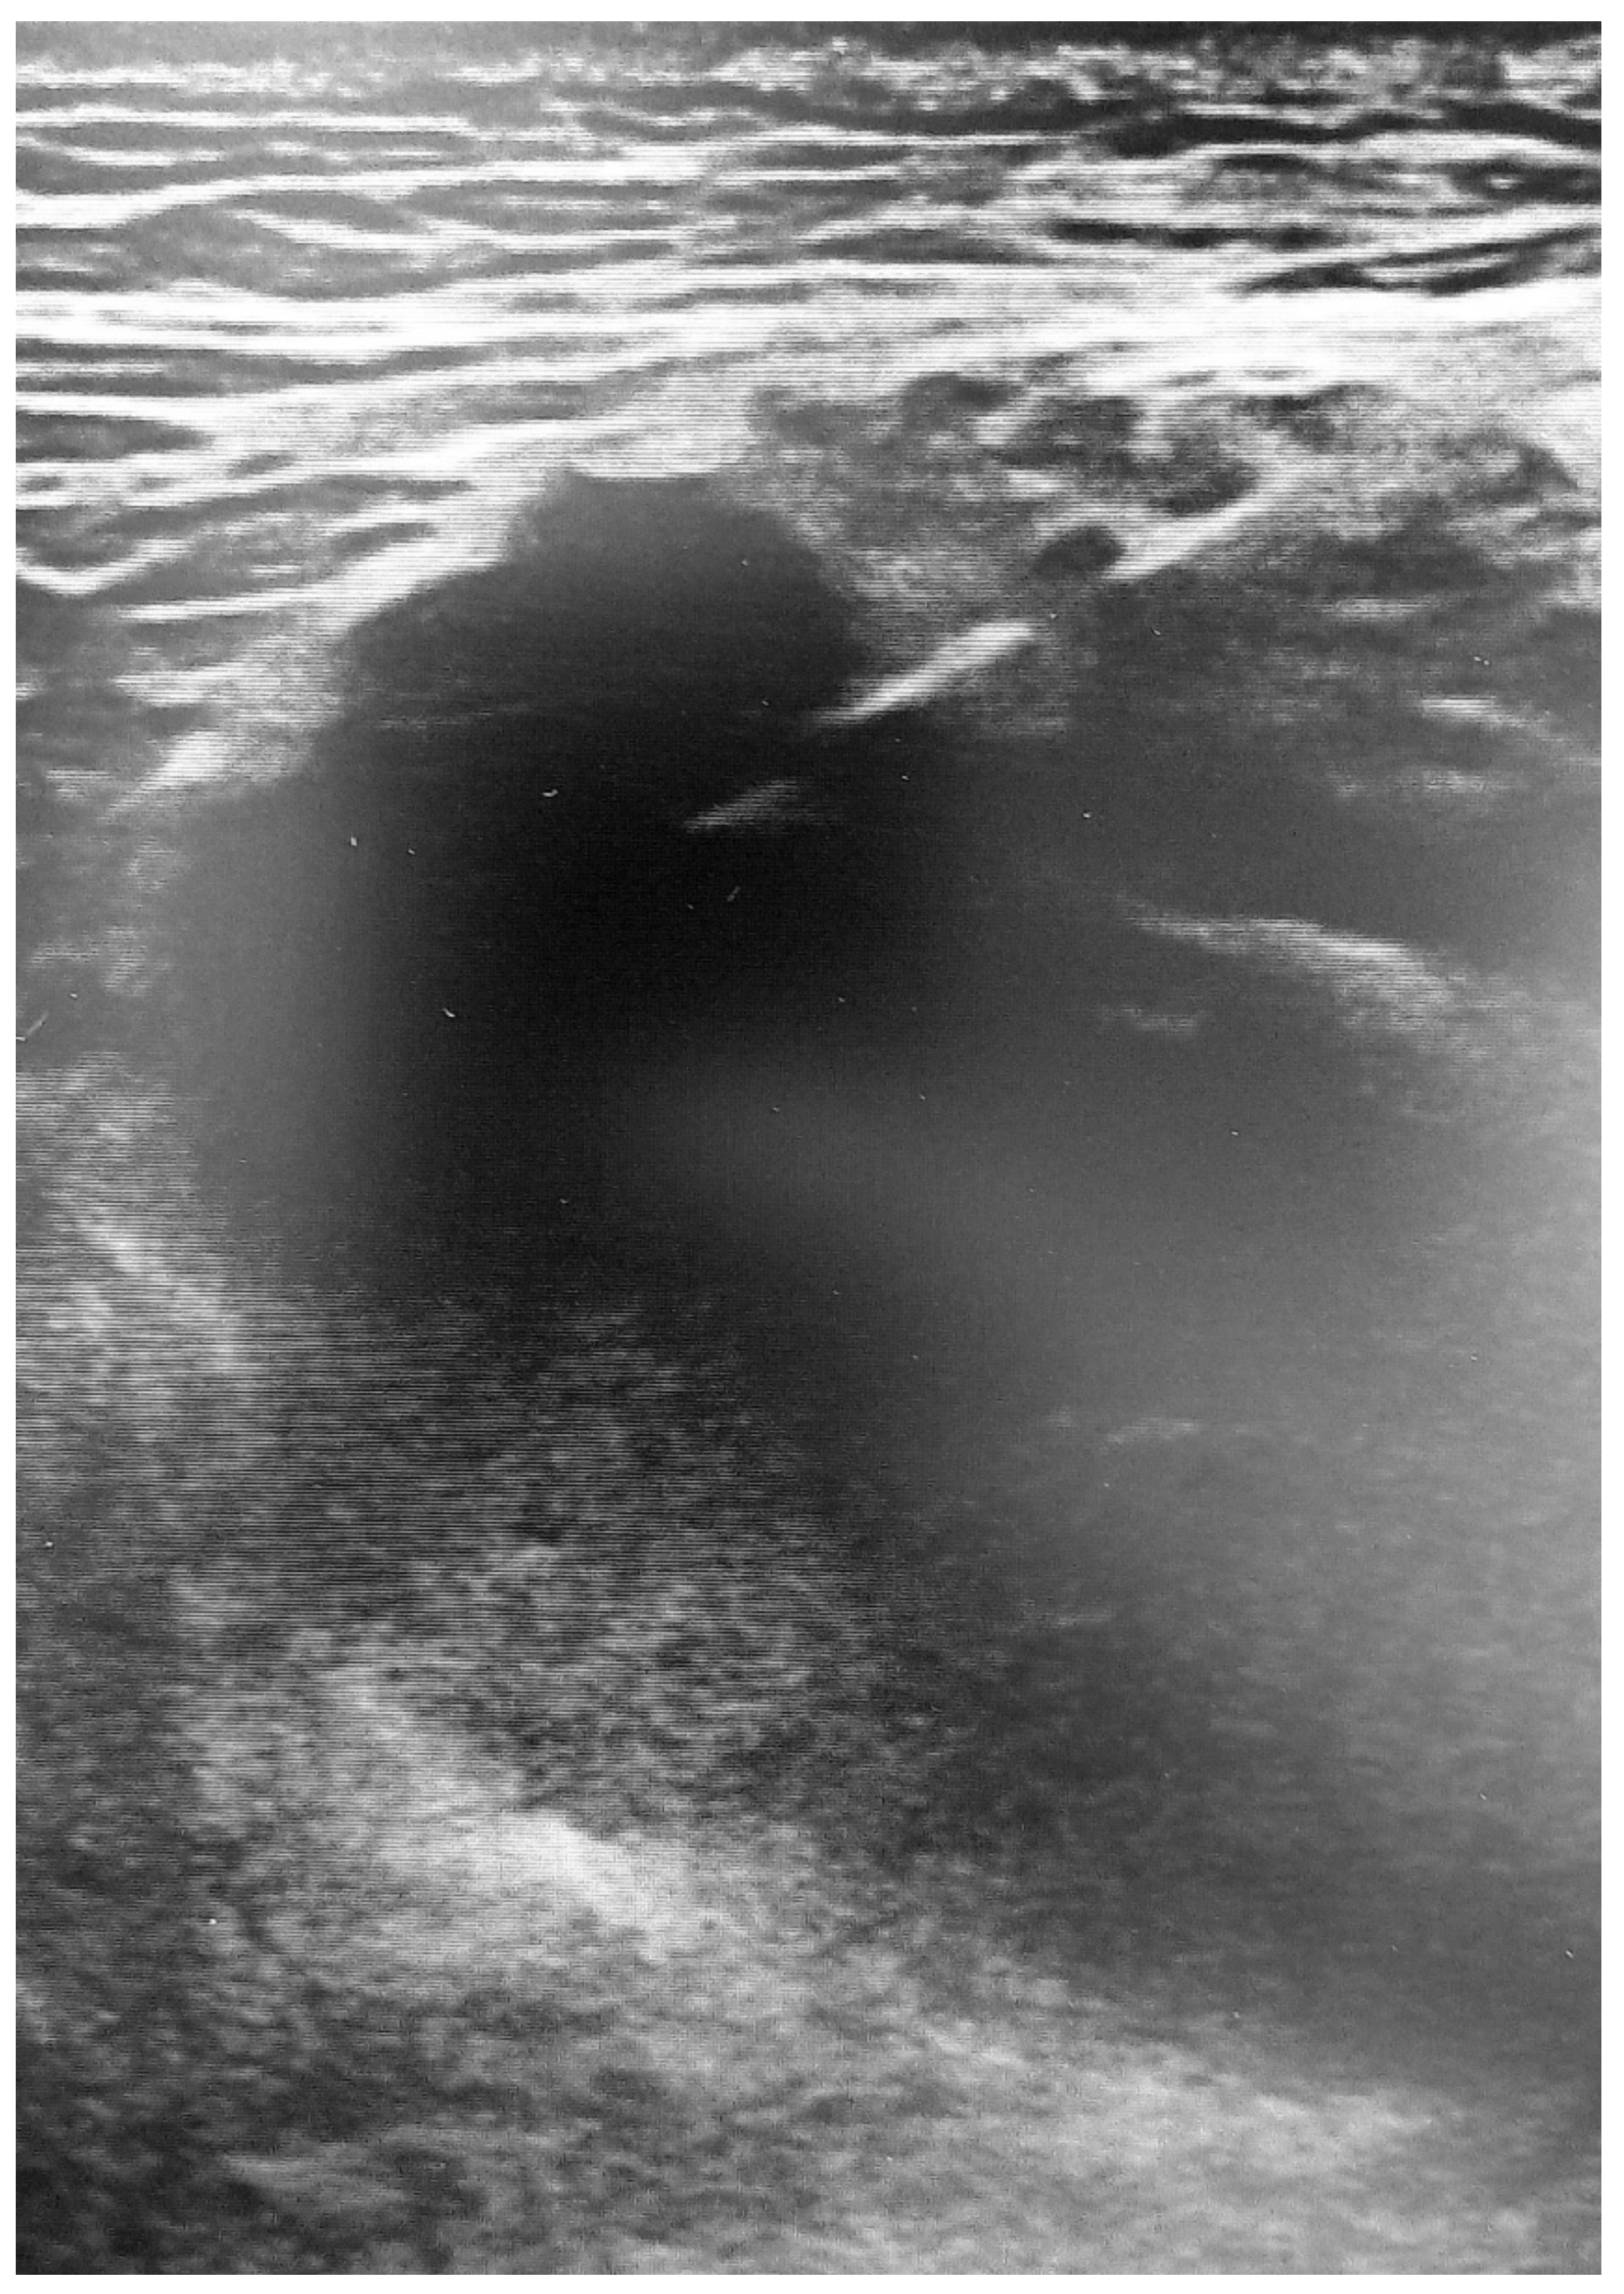

5. Ultrasound Findings of the Muscle Lesions

| Grade II | “20–50% cross-sectional area.” | “5–50% muscle involvement, partial muscle rupture, demonstrable hypo or an echoic gap, with “bell clapper” sign.” | “Discontinuity of muscle fibers in echogenic perimyseal striae; hypervascularity around disrupted muscle fibers; intramuscular fluid collection; partial detachment of adjacent fascia or aponeurosis.” | “Discontinuous muscle fibers; disruption site is hypervascularized and altered in echogenicity; no perimyseal striation adjacent to the MTJ.” |

| Grade III | “>50% cross-sectional area.” | “Complete tear of muscle or fascia, with extravasation of collection away from injured part of muscle.” | “Complete myotendinous or osteotendinous avulsion; complete discontinuity of muscle fibers and associated hematoma; “bell clapper” sign.” | “Complete discontinuity of muscle fibers; hematoma and retraction of the muscle ends.” |